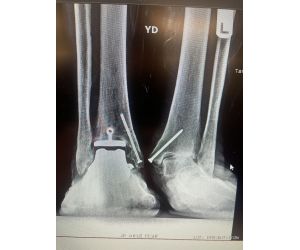

Progressive collapsing foot deformity with tibiotalar arthritis… a challenging problem

Jordan Sisto, DPM, FACFAS

Here we have a 69 y/o male with staged TAA on right that led to AVN talus and collapse which ultimately was revised to TTTA with great success -...